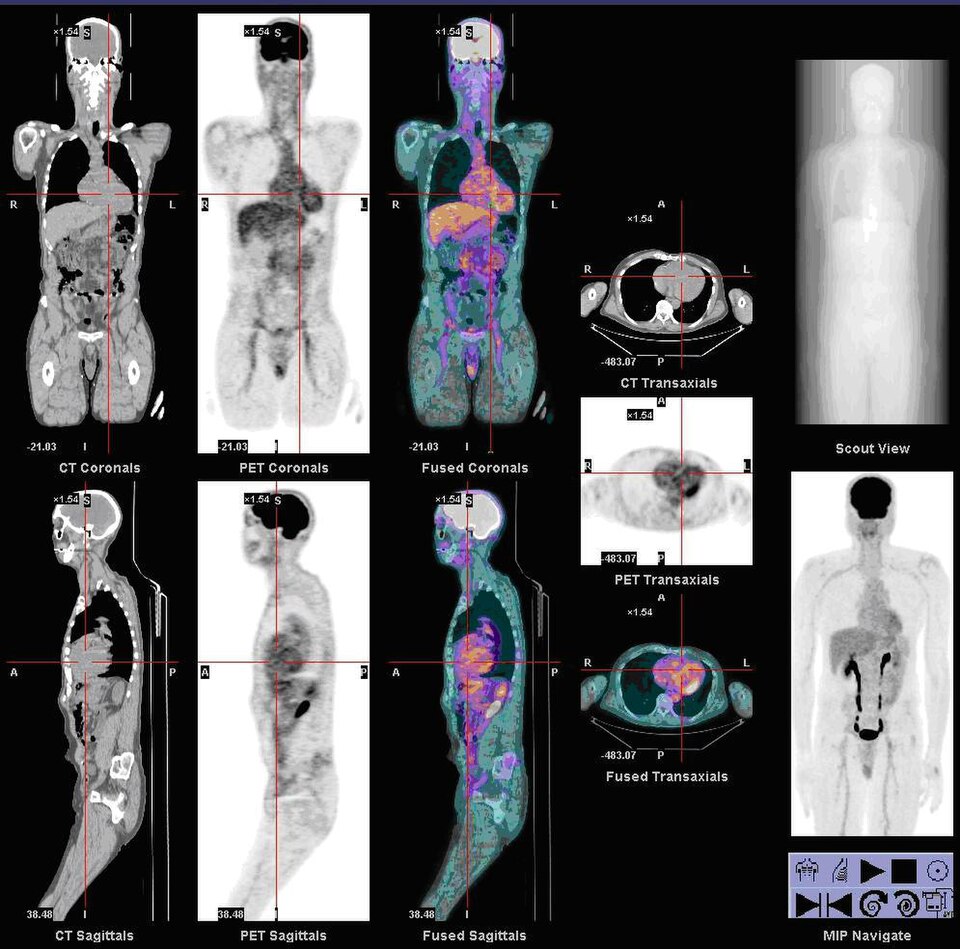

Whole-body PET/CT phantom with FDG-avid lesions in lung, liver, and lymph nodes for oncologic staging